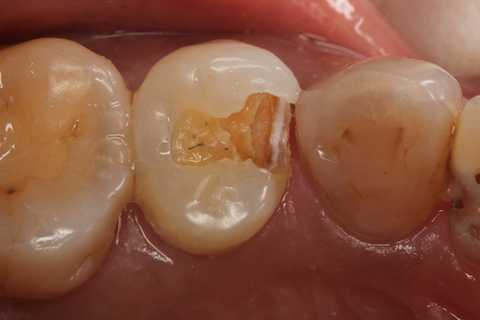

40代女性、左上5、冷水痛+

・・この歯は今回の他の症例よりも難しくないと思っていたのですが、まだ症状が続いているのかもしれない。ちょっと分からないが。

注意点はCRの接着面は新鮮歯質を確保して歯髄に近いところの軟化象牙質はあまり追求しないでも良い。α-TCPセメントの硬化と接着を妨げない程度に乾燥できれば良い。軟化象牙質は原材料のα-TCPと多少の水分があれば自然に再硬化するようだ。

この症例はストリップスを使っていない。使わない方が確実に充填できると思う。

では時系列でどうぞ